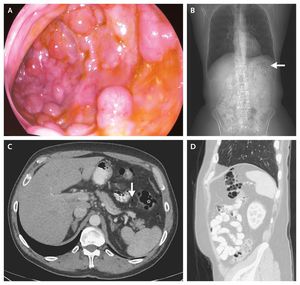

What is the diagnosis? Adrenal cancer Echinococcal infection Meckel's diverticulitis Pneumatosis intestinalis Trichobezoar

Since the lesions had bluish hue and easily indented, pnuematosis intestinalis is suspected.. Ct revealed multiple air pockets in the intestinal wall at the splenic flexure (image b) and some free intraperitoneal air (image c).Pneumatosis intestinalis is diagnosed by the presence of air pockets in the intestinal wall. the condition may also occur in a benign context and is no longer considered a disease but rather a sign, in most of the cases patient required no specific treatment and has remained asymptomatic,. It was the case of new England journal.....